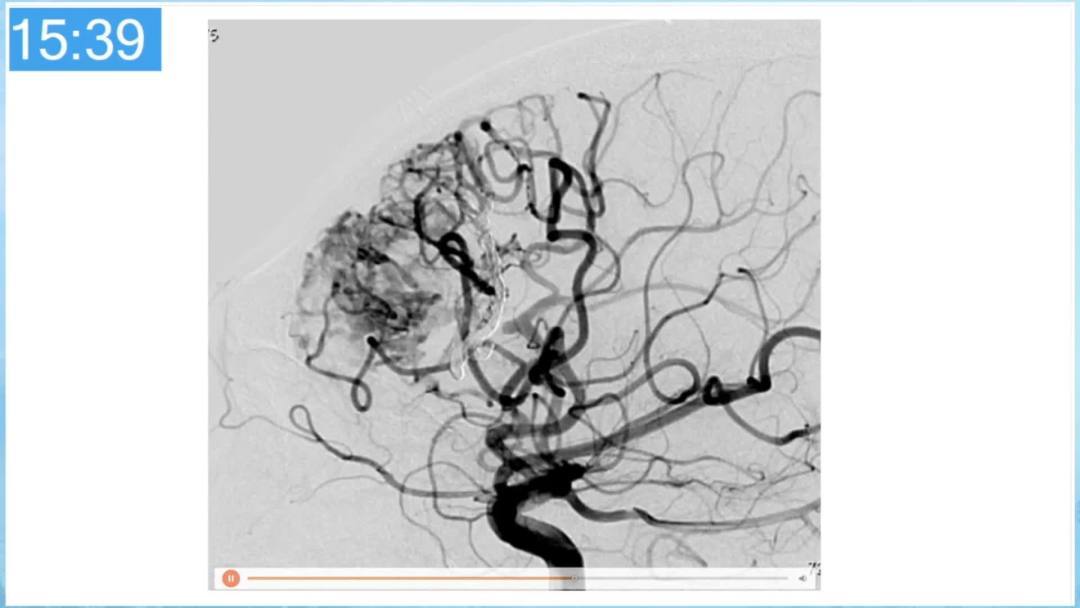

合理的复合平台下的综合治疗,针对每一个病变对应不同方法安全性分析,不预设、不排斥,每种技术发挥到最佳,互相保障。

本期为大家特别分享:空军军医大学唐都医院邓剑平教授的精彩会议内容《颅内动静脉畸形的复合手术治疗》,欢迎大家阅读和分享!